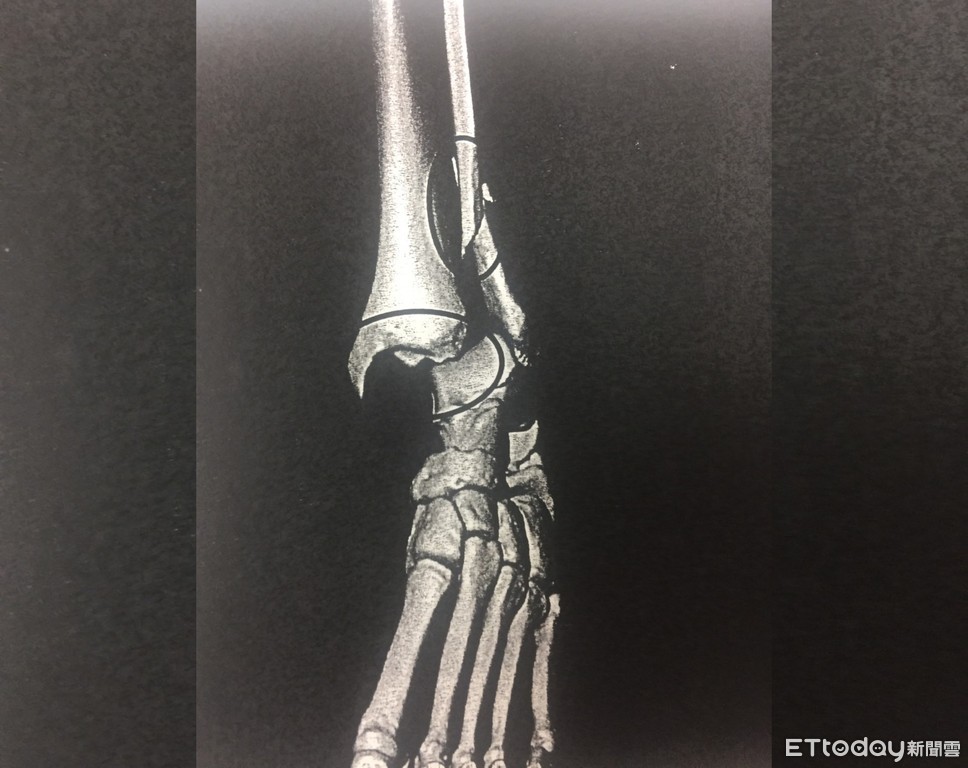

▲林姓男子指稱自己遭斧刃腳偷襲,導致腳骨斷裂。(圖/記者陳豐德翻攝)

新北市一名熱愛武術「八極拳」的林姓男子,2017年2月間與武術社團的張姓武友對練時,張男因數次無法破解招式,竟惱羞成怒使出禁忌招式「斧刃腳」攻擊,造成林男腳骨斷裂、腳踝脫臼,雙方事後調解未果,林男憤而提告傷害。北地院法官認為,張男使用禁招,且犯後態度惡劣、無悔意,依傷害罪判刑6月。

2017年二月間36歲的林姓男子在新莊體育館參加武術社團練習,結束後林男隨即找上張男切磋,前兩回合張男皆位居下風,遲遲無法破解招式,就在林男收手之際,張男突然出腳偷襲,造成林男右腳踝受傷倒地,送醫檢查發現左腳腓骨斷裂腳踝脫臼。

社員聽到哀嚎聲上前關心,通報救護車到場將林男送醫;社團教練趕抵現場查看,才驚覺林男是遭到社團的禁忌招式「斧刃腳」所傷,由於此招專門攻擊膝蓋或腳踝關節處,遭擊中者輕則挫傷,重則斷骨,所以平常練習時皆嚴禁使用。